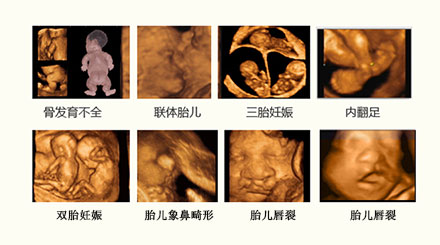

四维彩超是准爸准妈们热衷的孕检项目之一,肚子里的宝宝到底长得像谁?身体发育的是不是很好啊?这些,是每个准父母都渴望知道的。云南协和妇产医院引进的美国GE-E8四维彩超诊断仪,可直观、立体、多方位观察孕妇宫内胎儿的活动图像、生长发育情况,将胎宝宝的模样和动作制作成照片或VCR,成为“宝宝出演的一部微电影”。

此时是做四维彩超的最佳时间,这个时期胎儿局部结构及运动状态比较清晰,成像效果也比较好,可及时发现严重的胎儿畸形,诊断胎儿结构异常的准确率可达到95%-98%

美国GE-E8四维彩超,它是目前较先进的彩色超声设备,能360°立体展示胎儿各器官的发育情况,是应用于胎儿产前排畸及缺陷儿终极诊断、并完整记录胎儿宫内高清动态的尖端设备,其判断准确,有效的降低了误判等情况的发生。